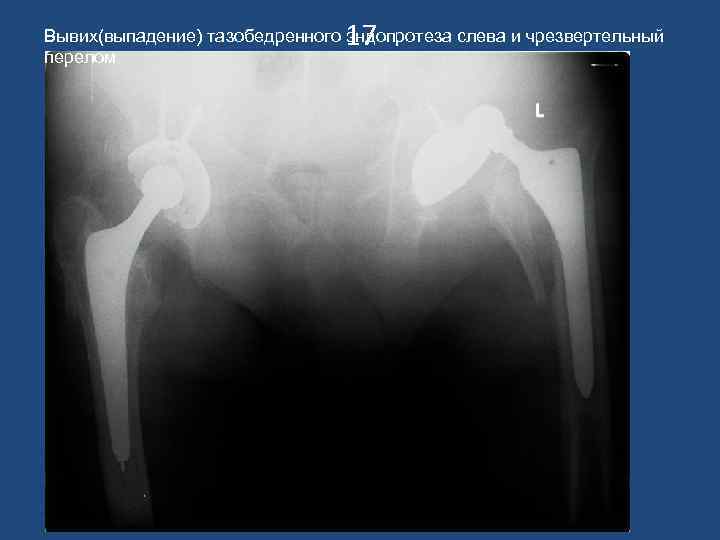

17 Вывих(выпадение) тазобедренного эндопротеза слева и чрезвертельный перелом